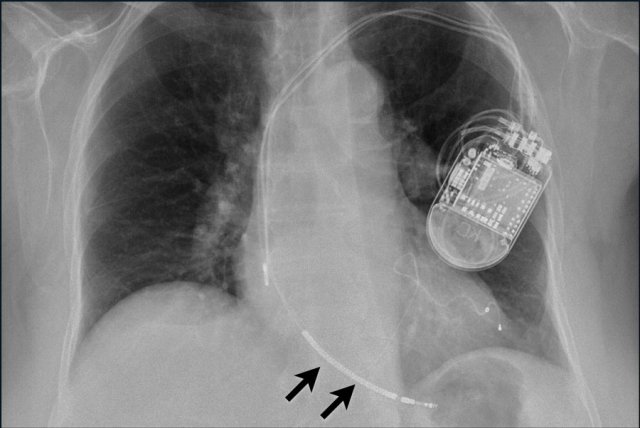

The findings are:

• Two epicardial leads connected to pacemaker

• ICD

• two leads to right ventricular apex

• one lead contains two shock coils

• tricuspid valve (arrows)

• mitral valve